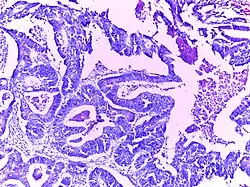

![]() | Mucinous cystadenoma | Micrograph showing Mucinous Cystadenoma of ovary. The cyst wall is lined by tall columnar epithelium and filled with mucin. | Category: Histopathology of mucinous cystadenoma | Mucinous cystadenoma |